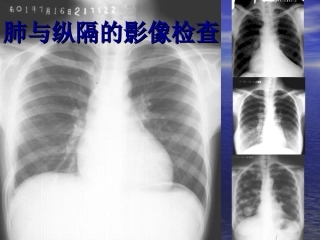

肺与纵隔的影像检查肺与纵隔的影像检查1.1.了解它的影像学检查方法。了解它的影像学检查方法。2.2.能对各个检查方法作出准能对各个检查方法...